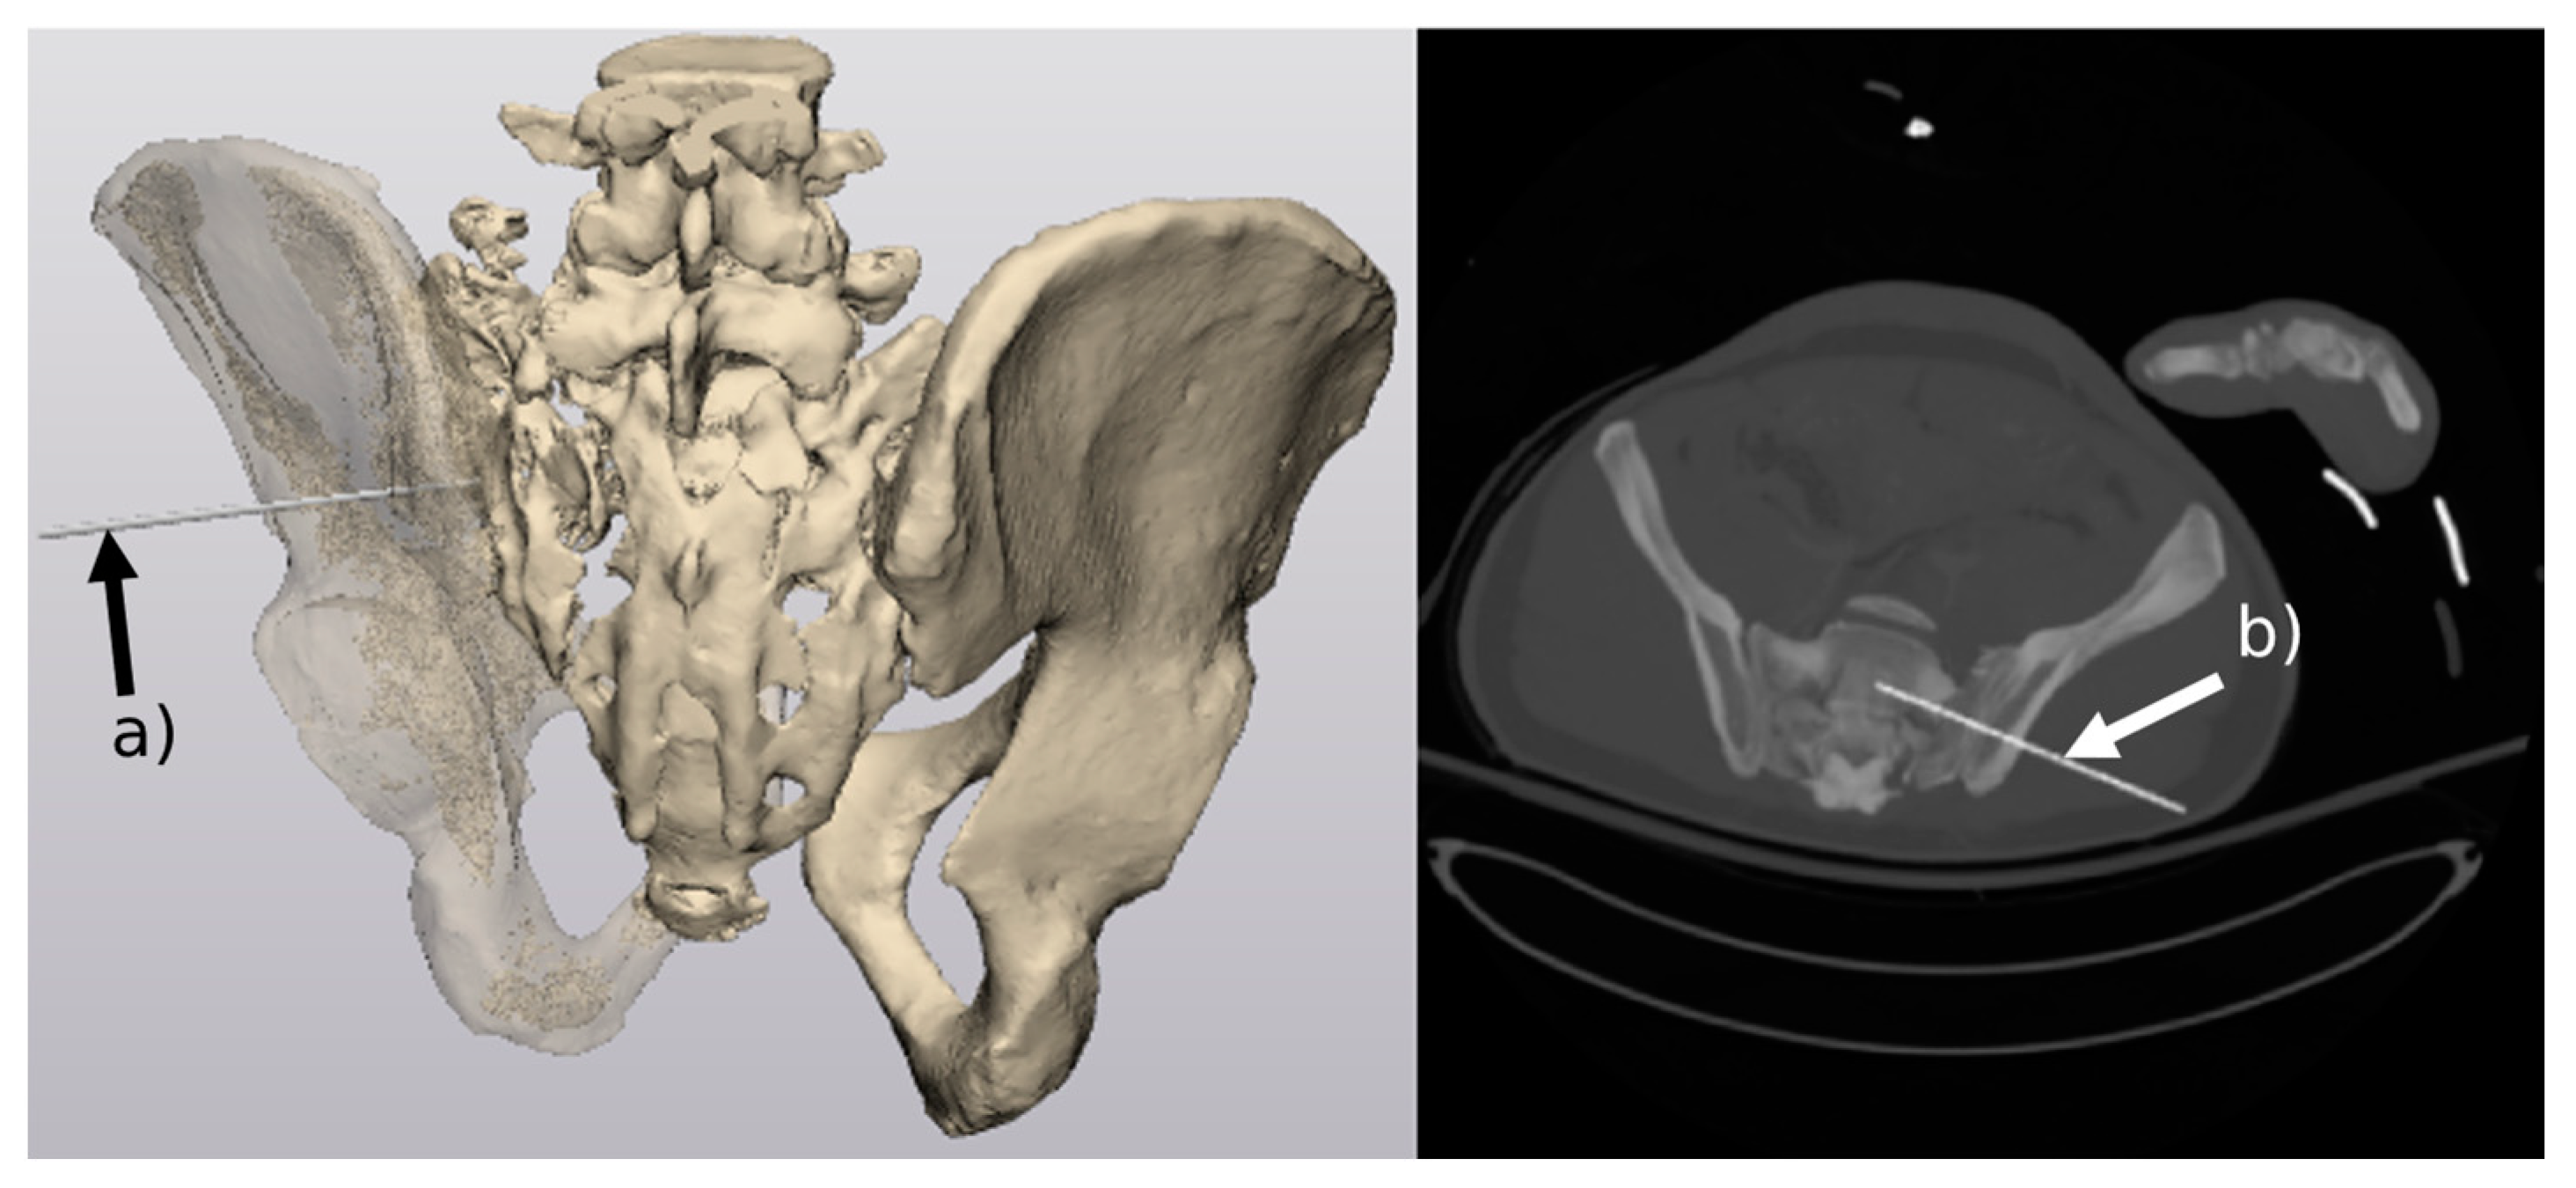

- Multiregional 3D segmentation model of pelvis area from CT images

- Generation of 3D models of the pelvis

3.1. Generation of 3D Models of the Pelvis